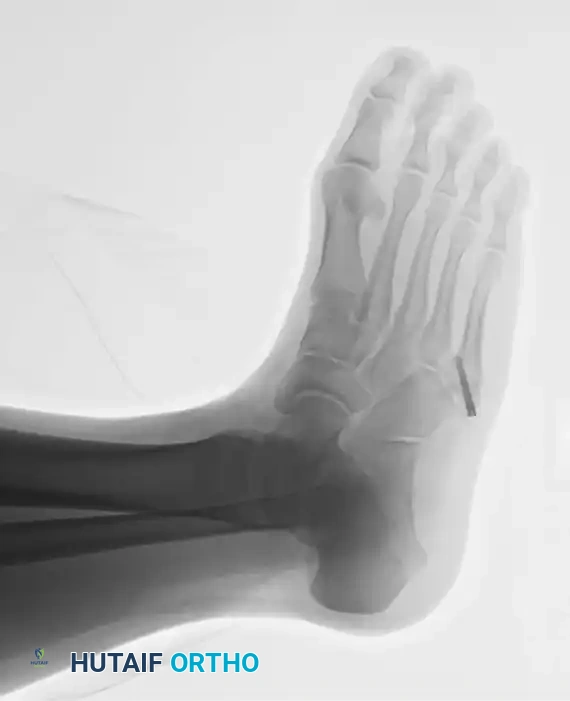

PREOPERATIVE PLANNING AND IMAGING

Standard weight-bearing anteroposterior (AP), lateral, and oblique radiographs of the foot are mandatory. The oblique view is particularly useful for profiling the fracture line at the metaphyseal-diaphyseal junction.

In cases of delayed union or nonunion, advanced imaging such as a Computed Tomography (CT) scan may be warranted to assess the extent of medullary sclerosis and to precisely measure the canal diameter. The medullary canal of the fifth metatarsal is not perfectly straight; it exhibits a lateral and plantar bow. Preoperative templating is critical to select a screw diameter that achieves cortical purchase without causing iatrogenic lateral cortical blowout.

- Fluoroscopic Confirmation: Advance the wire under multi-planar fluoroscopy. Ensure the wire passes the fracture site and sits centrally within the narrowest portion of the diaphysis (the isthmus).

- Confirm the drill's location via AP and lateral radiographs. The drill should cross the fracture site and engage the diaphyseal cortex without breaching it.

5. Screw Selection and Insertion

- Measurement: Estimate the length of the screw from the intraoperative radiographs. The screw must be long enough to bypass the fracture site and engage the diaphyseal isthmus, ensuring all threads are distal to the fracture line to allow for interfragmentary compression.

- Insertion: Place the screw over the guide wire. A 4.5mm to 5.5mm partially threaded screw is typically utilized, depending on the patient's canal diameter.

- Head Burial: It is imperative to countersink or bury the head of the screw into the tuberosity. A prominent screw head will cause severe irritation to the peroneus brevis tendon and overlying skin, often necessitating a second surgery for hardware removal.

- Verify final screw placement, fracture reduction, and compression with orthogonal radiographs.